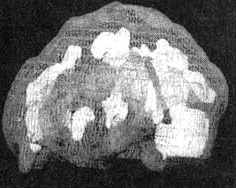

Мозг Роба. Результаты сканирования SPECT

Трехмерное изображение — активный мозг, вид сверху.

До лечения: обратите внимание на выраженное усиление активности в поясной системе (см. стрелку).